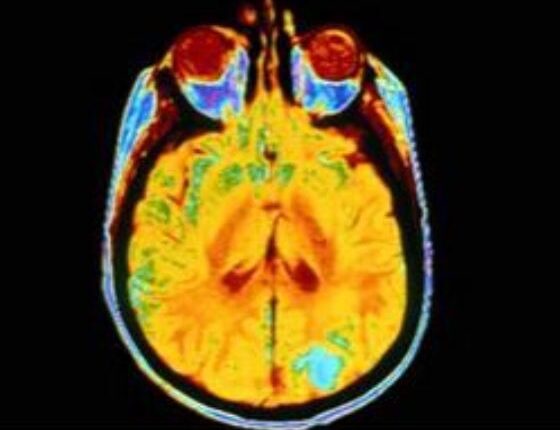

Ο όγκος του εγκεφάλου εμφανίζεται όταν τα μη φυσιολογικά κύτταρα στο εν λόγω όργανο αναπαράγονται με ανεξέλεγκτο τρόπο. Ωστόσο, δεν ξεκινούν όλοι οι όγκοι του εγκεφάλου υποχρεωτικά από το συγκεκριμένο όργανο.

Οι πρωτογενείς όγκοι του εγκεφάλου αναπτύσσονται αποκλειστικά από κύτταρα του εγκεφάλου, ενώ οι δευτερογενείς όγκοι του εγκεφάλου ξεκινούν από ένα άλλο μέρος του σώματος και στη συνέχεια εξαπλώνονται στον εγκέφαλο.